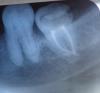

Kati789 Опубликовано 15 ноября, 2012 Поделиться Опубликовано 15 ноября, 2012 (изменено) Здравствуйте. 2,5 недели назад мне депульпировали и запломбировали каналы 7ки - внизу справа. Во время депульпирования я ничего не чувствовала, врач сделала рентген снимок и сказала корни пройдены, усадив в кресло стала вдавливать своим инструментом пломбировочный материал - в этот момент меня пронзила сильная боль, на что врач заметила - отходит заморозка. Хотя обычно после ультракаина, который мне ставят заморозка отходит 5 часов. В течении недели меня мучили сильные постпломбировочные боли, к зубу нельзя притронуться, десна опухла. Врач мне прописала пропить ципролет 7 дней и принимать найз. Во время приёма в десну поставила линкомицин. Распломбировывать зуб она не стала, объяснив это тем, что зуб очень хорошо запломбирован. Чувствительность зуба сохранилась и на второй неделе, опухлость с щеки спала. Через две недели я сделала снимок вылеченного зуба. На снимке очень отчетливо и хорошо видно, как пломбировочный материал из одного канала выведен за корень зуба в десну.. Стоматологи меня уверяют, что в этом ничего страшного нет и многие с такой проблемой живут годами и ставят на них коронки. Чем мне всё это грозит и можно ли этот дефект как-то перелечить. И я могу требовать это от той стоматологической клиники, где мне лечили зуб. Извините за длинное сообщение. Изменено 15 ноября, 2012 пользователем Kati789 Ссылка на комментарий

Снежана Опубликовано 15 ноября, 2012 Поделиться Опубликовано 15 ноября, 2012 здравствуйте. по снимку у вас зуб запломбирован очень хорошо, небольшое выведение пломбировочного материала считается допустимым, а в некоторых методиках пломбирования даже предпочтительным. Ссылка на комментарий

shishok Опубликовано 15 ноября, 2012 Поделиться Опубликовано 15 ноября, 2012 Возможно такая "бурная"реакция возникла у Вас как следствие перегрузки зуба(отсутствует шестой зуб и восьмой,видимо,тоже не в прикусе). Ссылка на комментарий